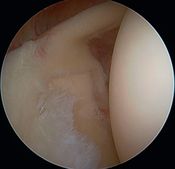

Walch et al. developed the theory of isolated posterosuperior impingement by publishing a series of 17 arthroscopies performed in athletes who demonstrated pain in the cocking phase but lacked concomitant instability. They explain this symptomatology by mechanical impingement repeated at 90% of abduction, maximum external rotation and retropulsion (maximum extension), between the greater tubercle and the posterosuperior glenoid rim, causing partial tears in the posterosuperior rotator cuff and the facing glenoid labrum (Figure, Movies).[11]

Posterosuperior impingement of Walch.

The appeal of this theory is that it is validated by simple observation when reproducing cocking and retropulsion movements under arthroscopic control, revealing the tears by repeated contact (Video).

They propose treatment by simple debridement, but the results are not as good as those reported by Andrews et al. Sonnery-Cottet et al., in a series of tennis players, reported an 80% return to sport, but only 50% at the same level.[12]

In a series of 75 throwing athletes with posterosuperior glenoid impingement, arthroscopic debridement was disappointing, with a return to the same sports level in only 16%. The authors found 89% partial rotator cuff tears, 90% labral tears (all posterior, except 3), as well as osteochondral tears affecting the glenoid or humeral head. No bicipital tears were found in this series.[13]